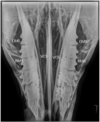

According to Chinkangsadarn T, Wilson GJ, Greer RM, Pollitt CC, Bird PS. in “An abattoir survey of equine dental abnormalities in Queensland, Australia”.

Identify the equine abnormality in b (arrows and star), c and d.